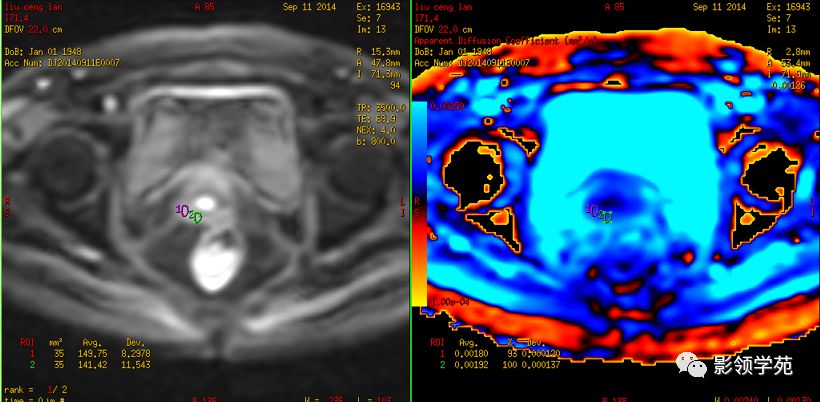

DWI:局限性高信号,癌组织ADC值<癌旁组织<小于正常宫颈组织

宫颈癌术后复发患者,DWI上病灶较T2 fs及T1+C更加明显

DWI显示淋巴结肿大